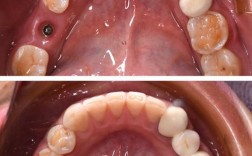

- 轻度拥挤/不齐: 如果只是轻微的牙齿拥挤或扭转,排齐可能相对较快,大约6-9个月。

- 中度拥挤/不齐: 比较常见的牙齿拥挤或个别牙齿明显错位,排齐时间通常在9-12个月左右。

- 重度拥挤/不齐: 牙齿严重拥挤、扭转、甚至需要拔除牙齿才能排齐,排齐时间会更长,可能需要12个月甚至更久(18个月以上)。